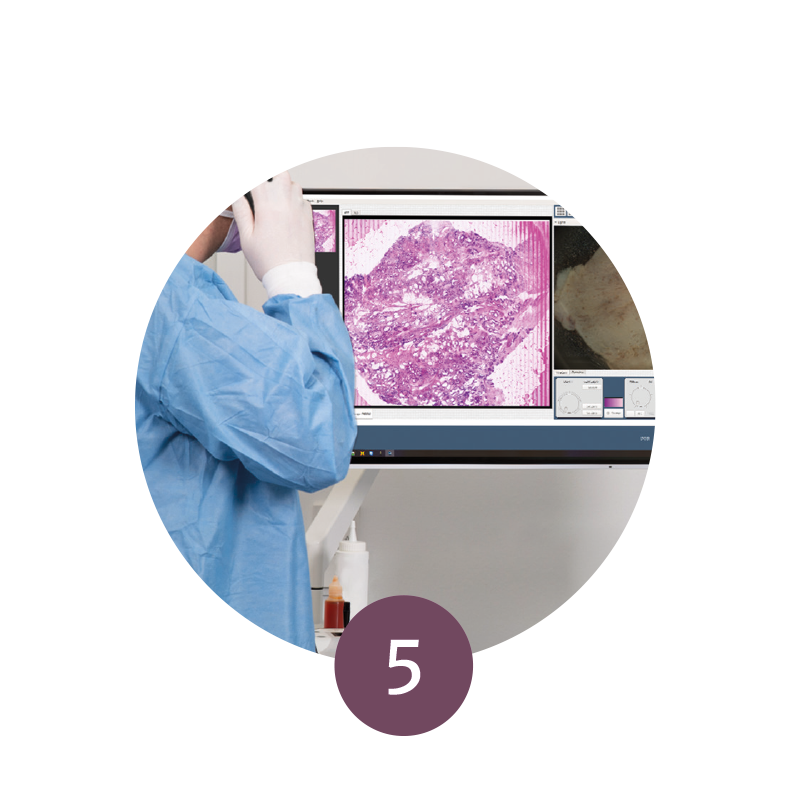

Step 5: Evaluation & Telemedicine

During the surgical procedure, the specimens can be evaluated microscopically and the procedure adapted accordingly.